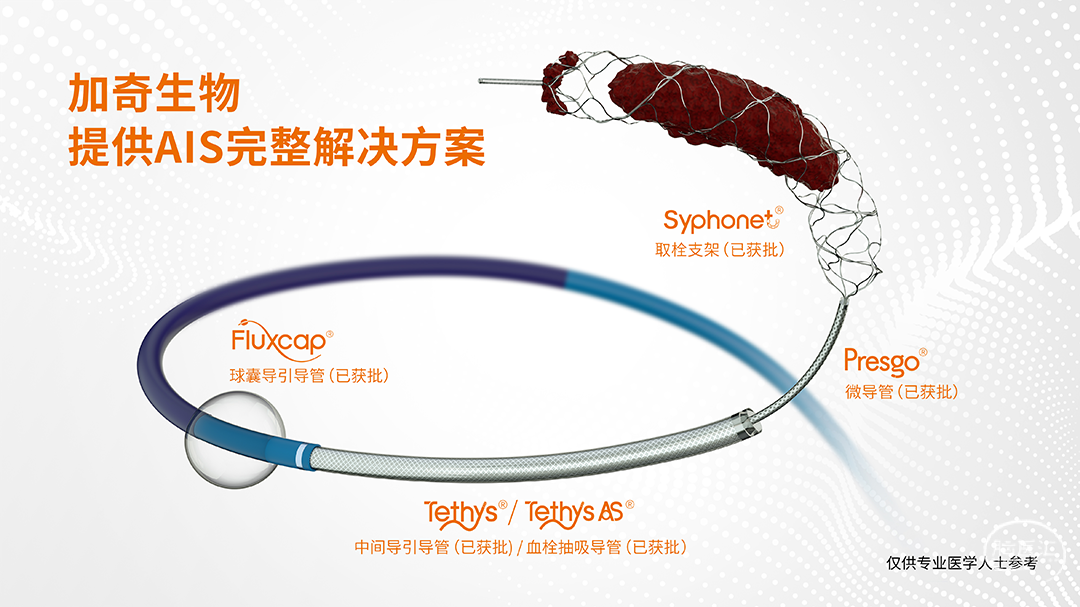

术中器械

结合头颅CT检查及临床症状(神志不清,失语,凝视,右侧肢体瘫痪),考虑左侧大脑中动脉上干栓塞为责任病变,根据患者病情,经研判后准备给予镇静下脑动脉血栓取出术,沿股动脉鞘送入6F长鞘(内衬5F多功能导管,预接Y阀及压力滴注)至左侧颈总动脉远端,撤出泥鳅导丝及多功能导管,沿长鞘送入5F 125cm Tethys AS®血栓抽吸导管(内衬0.014inch 215cm DCwire®微导丝及0.021inch 150cm 微导管)至左侧大脑中动脉远端,Tethys AS®血栓抽吸导管精准到位,撤出DCwire®微导丝、微导管。

5F 125cm Tethys AS®血栓抽吸导管外接50ml注射器负压抽吸,关闭所有滴注,ADAPT技术,抽吸出黑色血栓成分,冒烟见血管再通,造影显示左侧颈内动脉、大脑中动脉、大脑前动脉及其分支显影好,前向血流TICI分级3级。

⾎管内介⼊治疗是颅内外大脑中动脉闭塞的标准治疗⽅式,其预后与再通时间、复流程度密切相关。精准的病变部位及性质的识别可减少不必要的检查,争取更短的开通时间。本案例为大脑中动脉分叉处混合血栓的取栓治疗,混合血栓具有一定韧性,且位于大脑中动脉分叉处,如首选支架取栓,取栓支架释放后血栓位置较易移动,无法固定并被支架完全包裹,不易取出,且栓子易反复在上下干之间停摆而无法实现完全再通。术中所使用加奇生物 Tethys AS®血栓抽吸导管,相较Tethys推送更加顺畅,到位更加优秀,一次取通,配合加奇生物 DCwire®微导丝 ,精准超选,节省手术时间,临床预后令人满意。